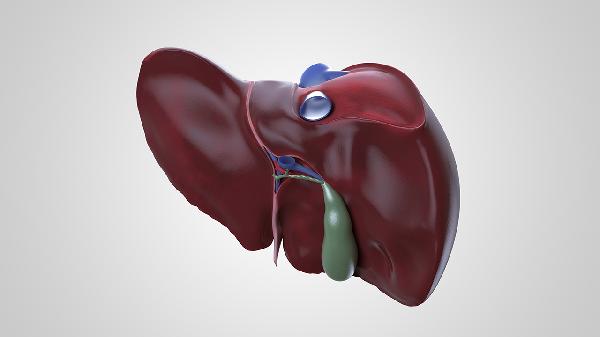

肝脏切除后通常可以再生,但再生能力与切除范围、个体健康状况等因素有关。肝脏是人体内唯一具有显著再生能力的器官,在部分切除后可通过肝细胞增殖恢复功能。

肝脏切除后的再生过程主要发生在术后3-6个月内。当切除范围不超过70%时,剩余肝组织可通过代偿性增生逐渐恢复原有体积。这一过程中,肝细胞会快速分裂增殖,同时胆管、血管等结构也会同步重建。术后1-2周即可观察到再生迹象,3个月左右达到再生高峰。再生后的肝脏在功能上可完全代偿,但解剖形态可能与原肝脏存在差异。影响再生速度的因素包括年龄、营养状况、基础肝病等,年轻患者、无肝硬化者再生能力更强。

当肝脏切除范围超过75%或存在严重肝硬化时,再生可能受限。这种情况下剩余肝组织难以完全代偿,可能出现肝功能不全。急性肝衰竭、严重脂肪肝等基础疾病也会显著抑制再生能力。对于这类患者,术前需精确评估剩余肝脏功能储备,必要时考虑活体肝移植等替代方案。术后需密切监测转氨酶、胆红素、凝血功能等指标,及时发现再生障碍。